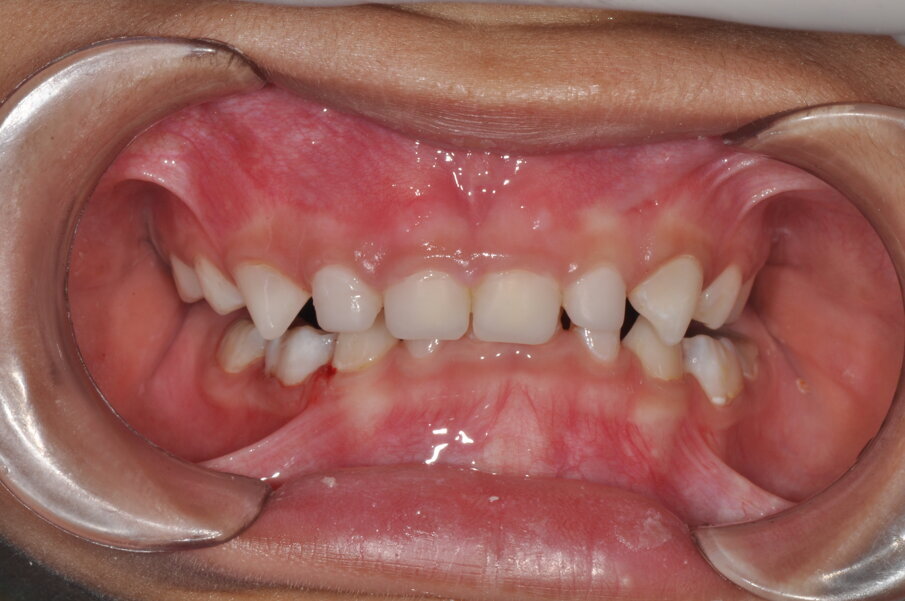

A 4-year-old girl was referred to the Children’s Dental Center in Gurgaon in India with the complaint of painful teeth when eating and the presence of unsightly maxillary anterior teeth. Clinical examination showed large carious lesions in the maxillary anterior teeth (Fig. 1). A radiographic examination showed pulpal involvement of caries in teeth #51 and 61 (Fig. 2).

Fig.1: Caries associated with the four front teeth.